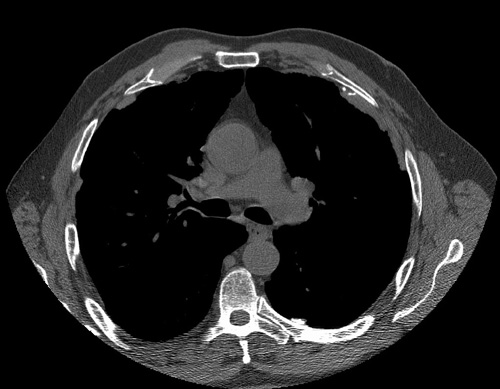

Inhale > Asbestos > Images > Asbestosis Case 1